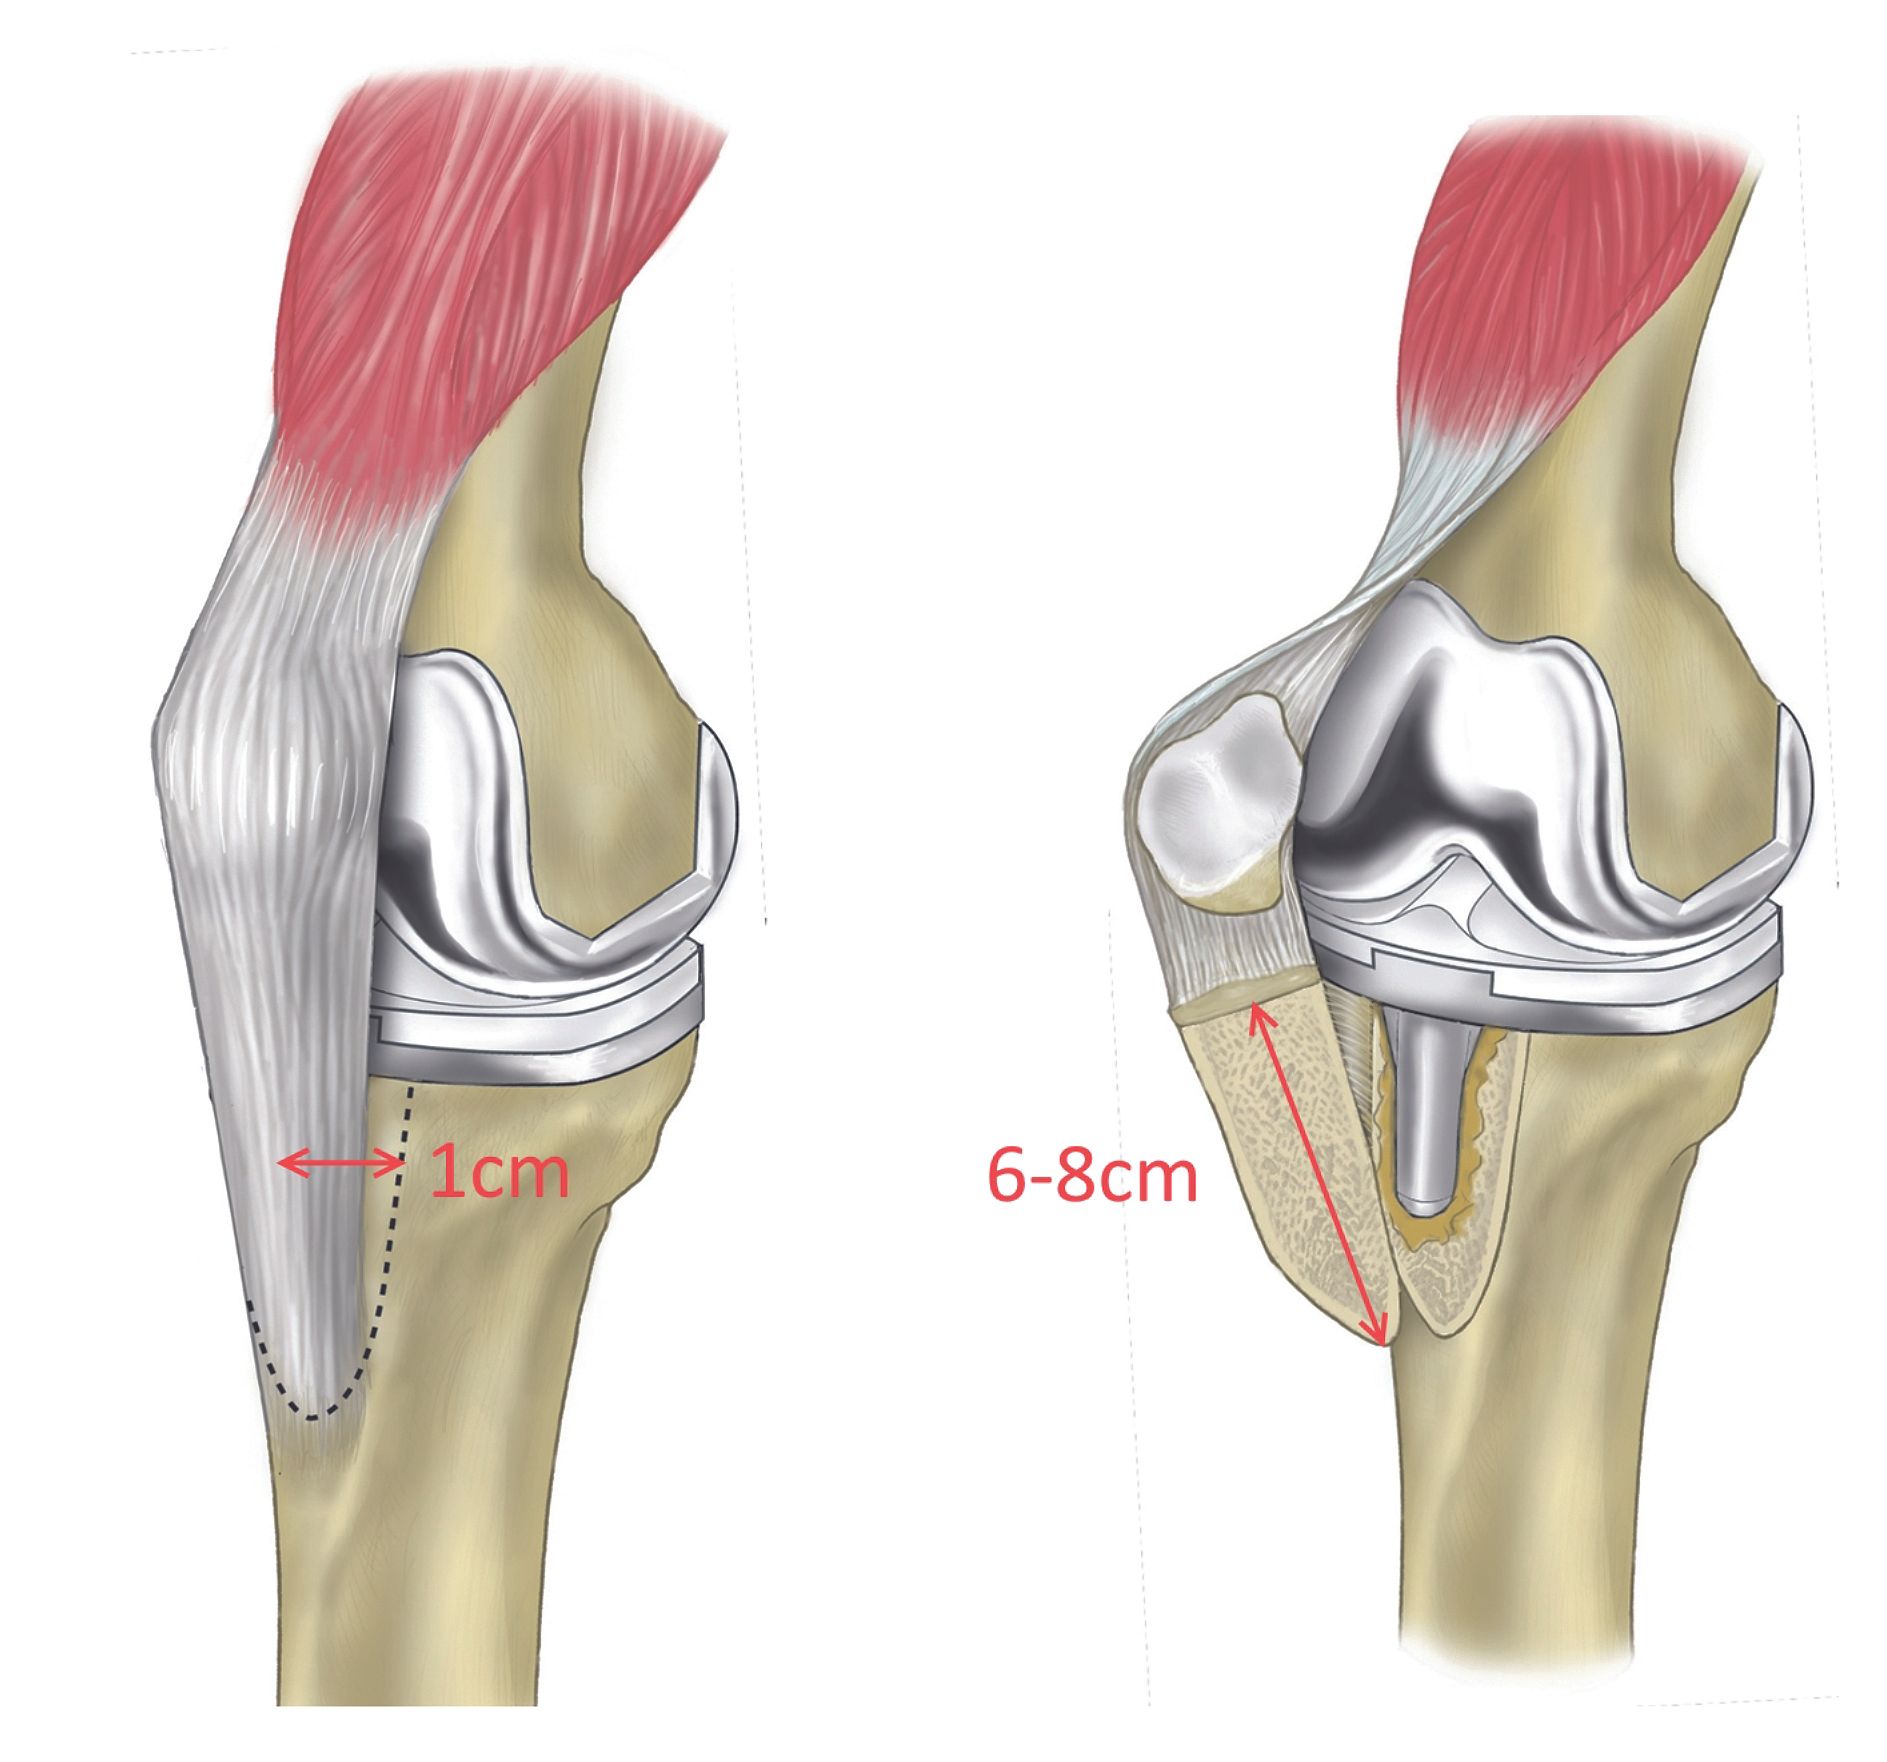

The clinical articles in this issue span a broad range of musculoskeletal conditions. Spinal pathology is addressed through a sublaminar osteotomy technique for lumbar spinal stenosis, while upper extremity care is represented by an update on treatment options for thumb arthritis. Hip preservation is examined via simultaneous periacetabular osteotomy and arthroscopically assisted management of cam-related pathology in acetabular dysplasia. Additional contributions address endoscopic piriformis tenotomy and sciatic nerve release and a modified Tibial Tubercle "Crest" Osteotomy (TCO) for extensile knee exposure.